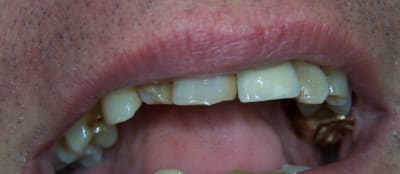

juilliet 2009 bridges provisoires sur ANKYLOS mise en charge immédiate sans scellement.

Chirurgie à COUFOULEUX, préparation prothétique et dispositif de forage à MONTASTRUC LA CONSEILLERE, dans notre belle campagne de France.